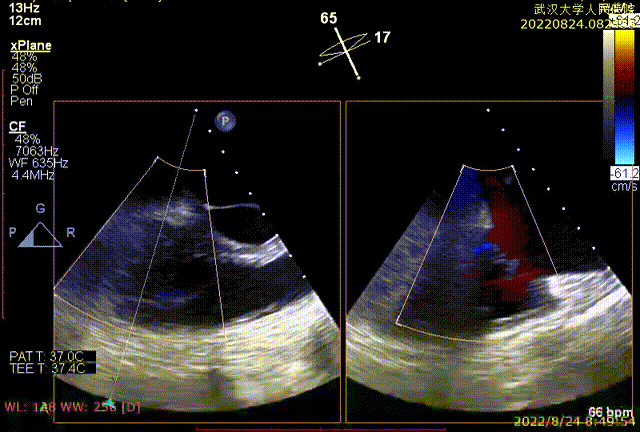

图2:术后即刻TEE

同时其瓣膜夹系统继承于申淇淇麟®经导管二尖瓣夹及可操控导引导管系统优秀设计,具备四个不同型号的夹子及瓣叶分开捕获能力,从而适用更加复杂多变的三尖瓣解剖。因该患者三尖瓣反流束较宽,瓣叶存在较宽的关闭裂隙,术中很好的利用了瓣叶分开捕获的功能,于前隔瓣区域行瓣膜缘对缘修复。植入一枚长宽夹子后,术后即刻患者反流减至轻度。患者术后恢复良好,出院前TTE提示三尖瓣轻度反流。